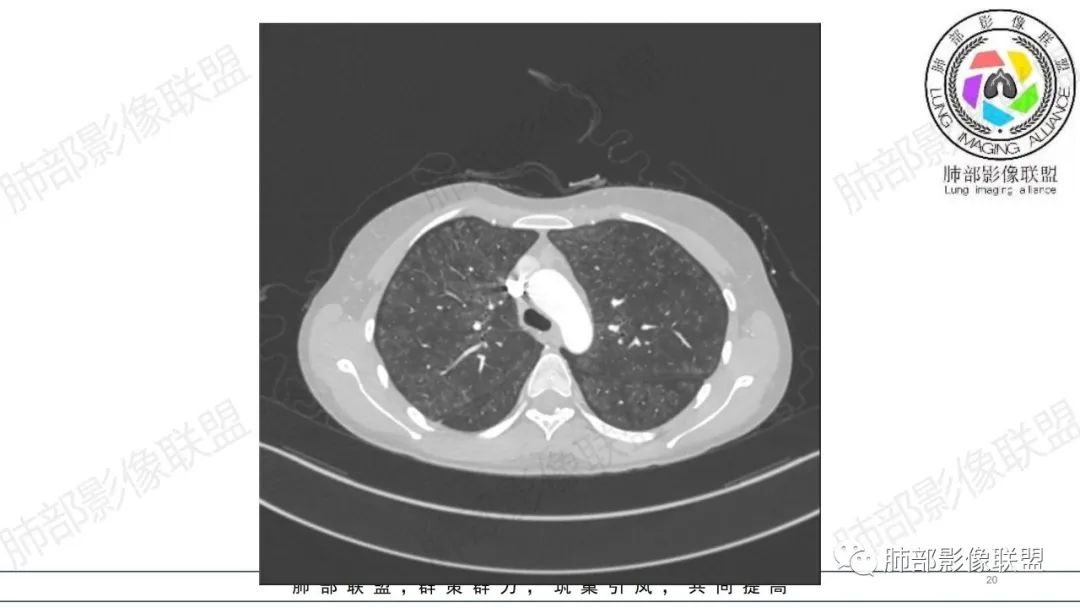

影像资料

34岁女性患者,“哮喘”病史30年,近期有可疑刺激性气体吸入史;因乏力半年,咳嗽、憋气、发热4天就诊;6.1CT提示双肺广泛毛玻璃影及粟粒样结节,胸膜下闲置及血管周闲置,可见树丫征,部分小叶间隔增厚。考虑:1.过敏性肺泡炎,有可疑刺激气体接触史,胸膜下闲置,广泛毛玻璃影,地图样分布,粟粒结节边界模糊,支持过敏性肺泡炎,但糖皮激素治疗效果不佳,且动态复查血常规血红蛋白进行性降低,过敏性肺泡炎 不符合;2.肺含铁血黄素沉积症:患者30“哮喘”病史,可能为肺含铁症状,肺部CT提示双肺弥漫毛玻璃影及粟粒结节影,中下肺明显,肺底部分小叶间隔增厚,近期咳嗽、憋气、发热,血常规血红蛋白进行性下降,考虑肺含铁急性期症状,但临床无咯血症状,肺含铁不典型。综合考虑:肺含铁血黄素沉积症>过敏性肺泡炎。

年轻女性 ,急性喘息发热,肺部影像弥漫磨玻璃密度,部分细小腺泡结节,胸膜下黑线显示,短期复查,病变密度增高,下肺明显,血管周围肺组织累及较少、且逐渐成小叶间隔分布。考虑弥漫肺泡内病变,并经淋巴道转移,下肺比上肺明显,多为免疫细胞功能下肺较强。1.过敏性肺泡炎,有相关病史,三层密度特点、头尾测分布,符合。2 肺泡微石症,多有钙化,且缓慢起病,病程不太符合,放待排。3 吸入相关肺损伤,有病史,疾病演变过程也符合渗出-肉芽肿改变,建议详细询问病史。4 感染性病变,结核?病变气道分布为主,如此弥漫且没有树丫不符合。5.巨细胞病毒,可以磨玻璃 结节 改变,没有免疫缺陷病史。最后考虑吸入所致 1过敏性肺泡炎、吸入性肺损伤 鉴别肺泡微石症。

肺内气腔磨玻璃结节,肝脾肿大,治疗后间质改变,弥漫大B可能